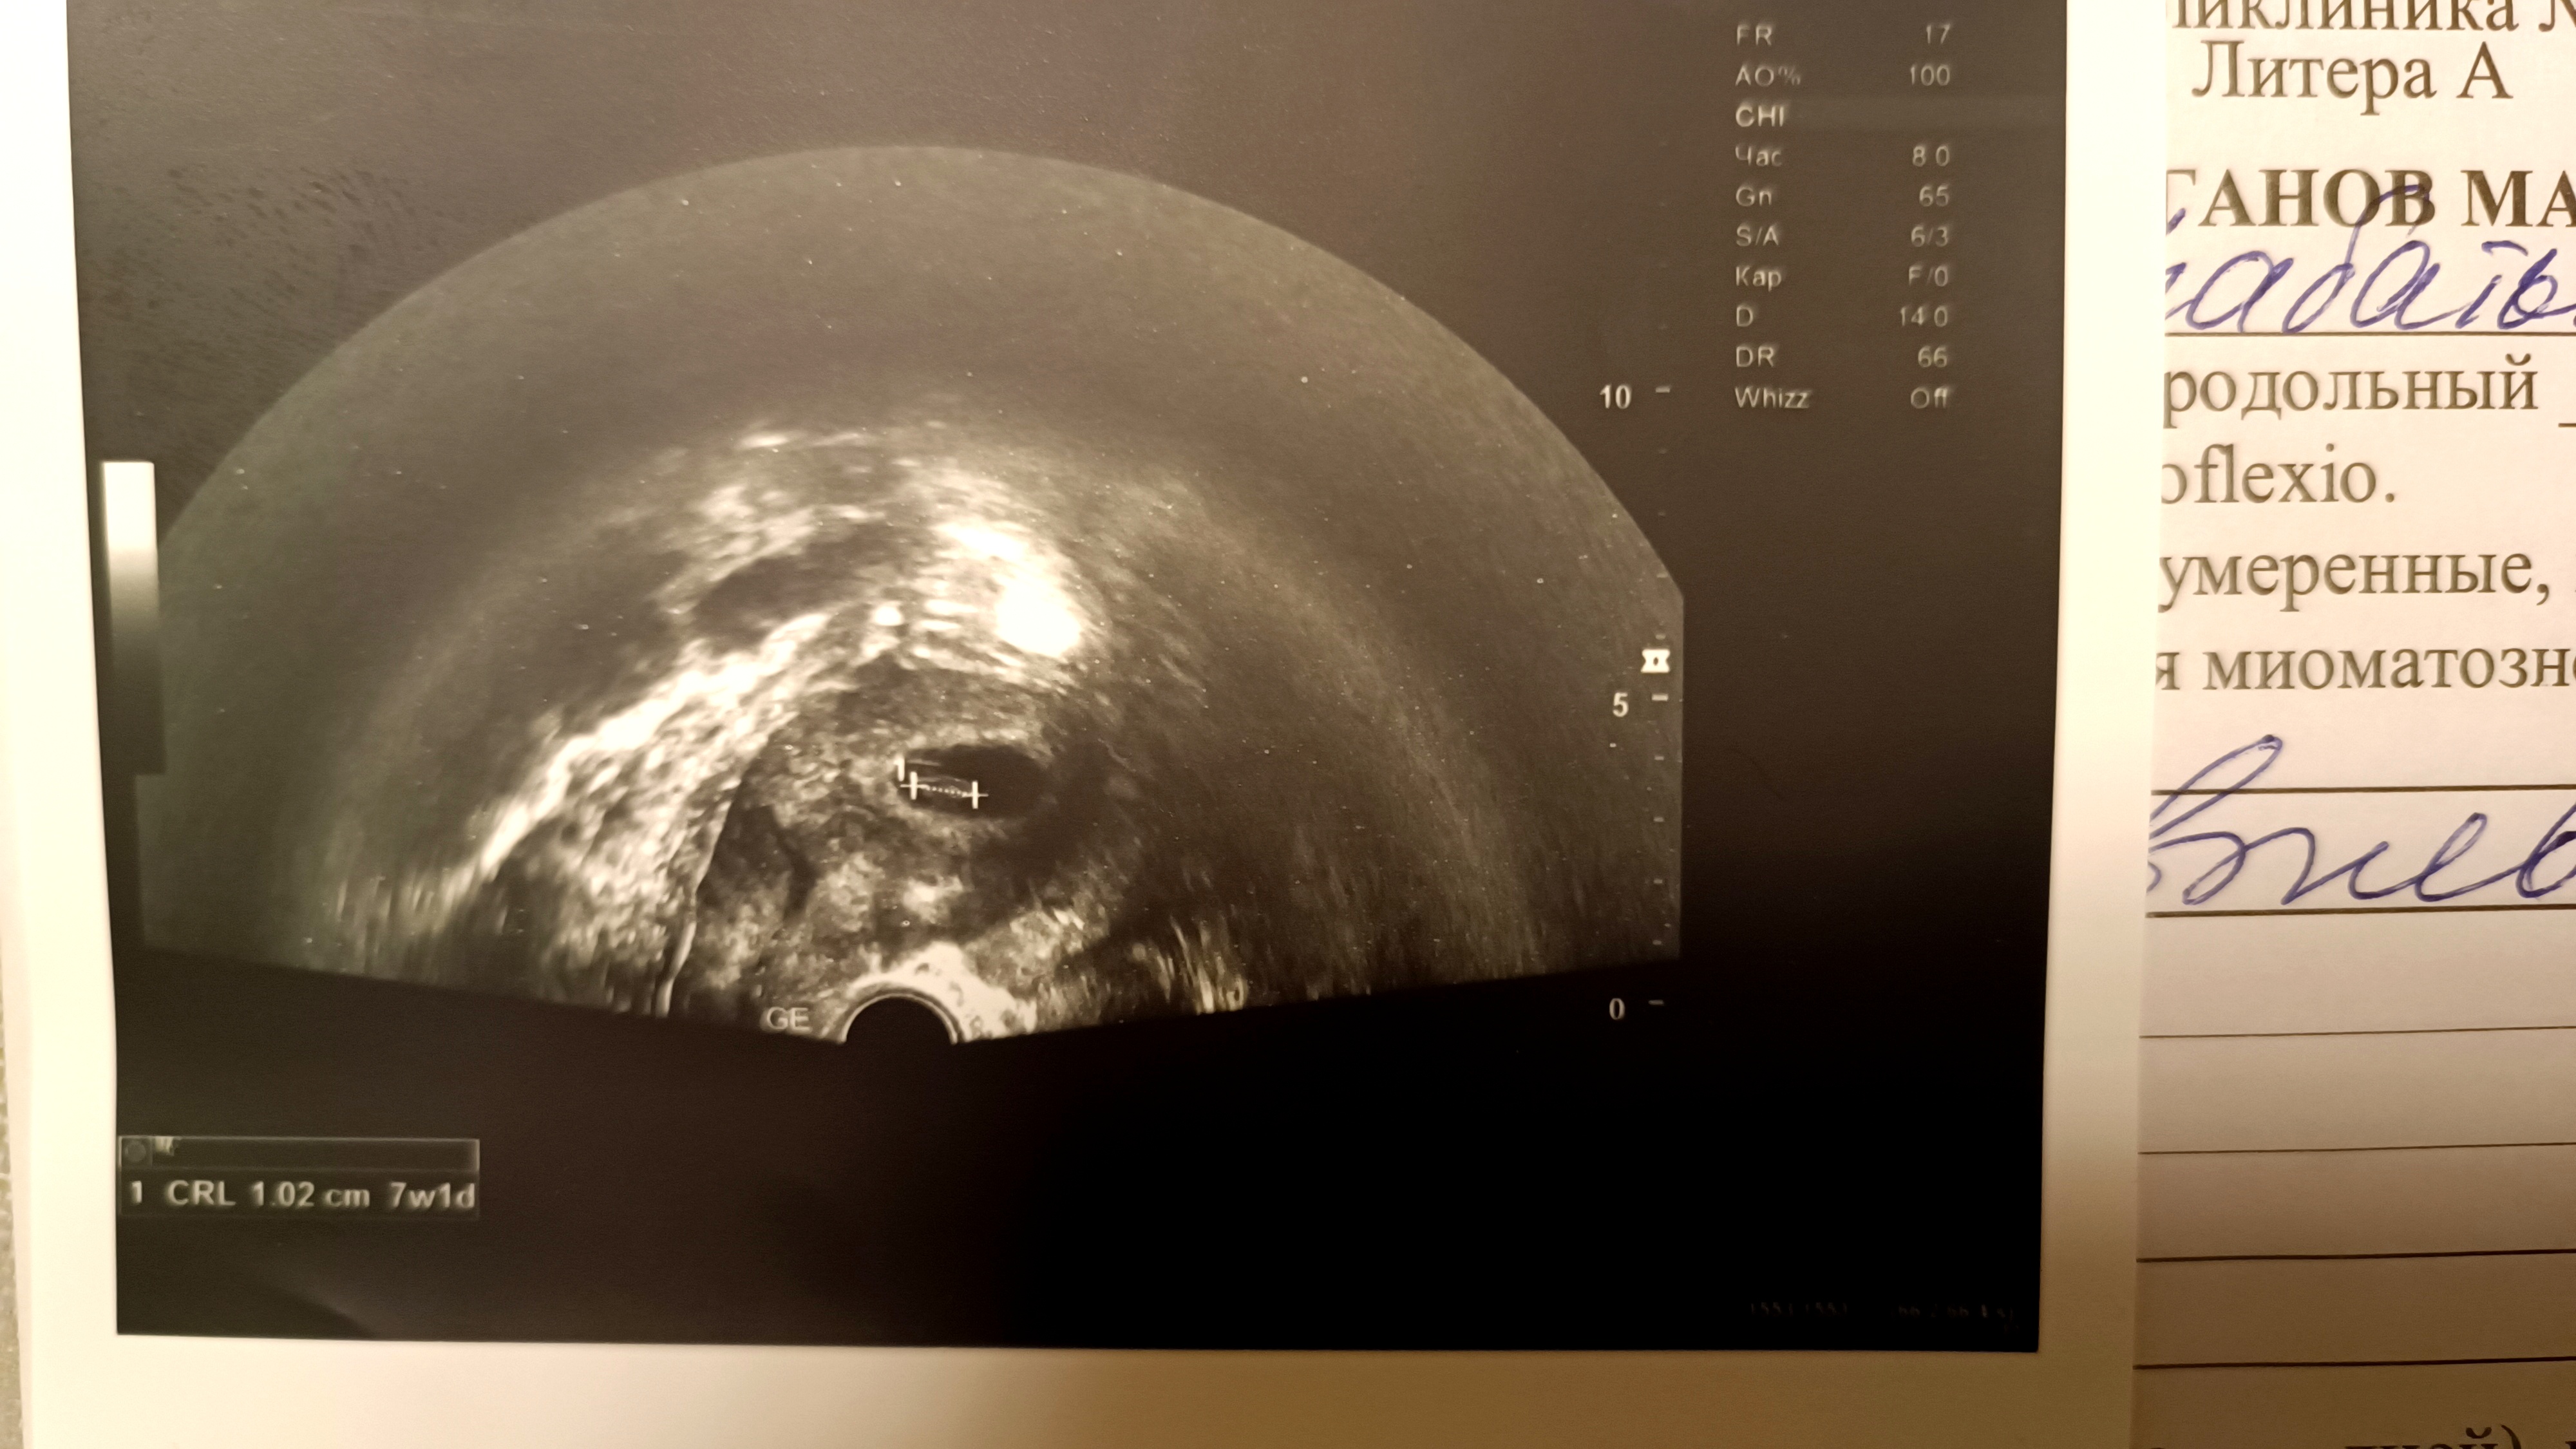

Наконец-то дождалась первое УЗИ.

Акушерский срок 6 недель 2 дня. Срок по УЗИ 7 недель. КТР 10 мм, сб +. ПЯ 38 мм.

Сработала правая сторона, где сохранена труба) Желтое тело справа.